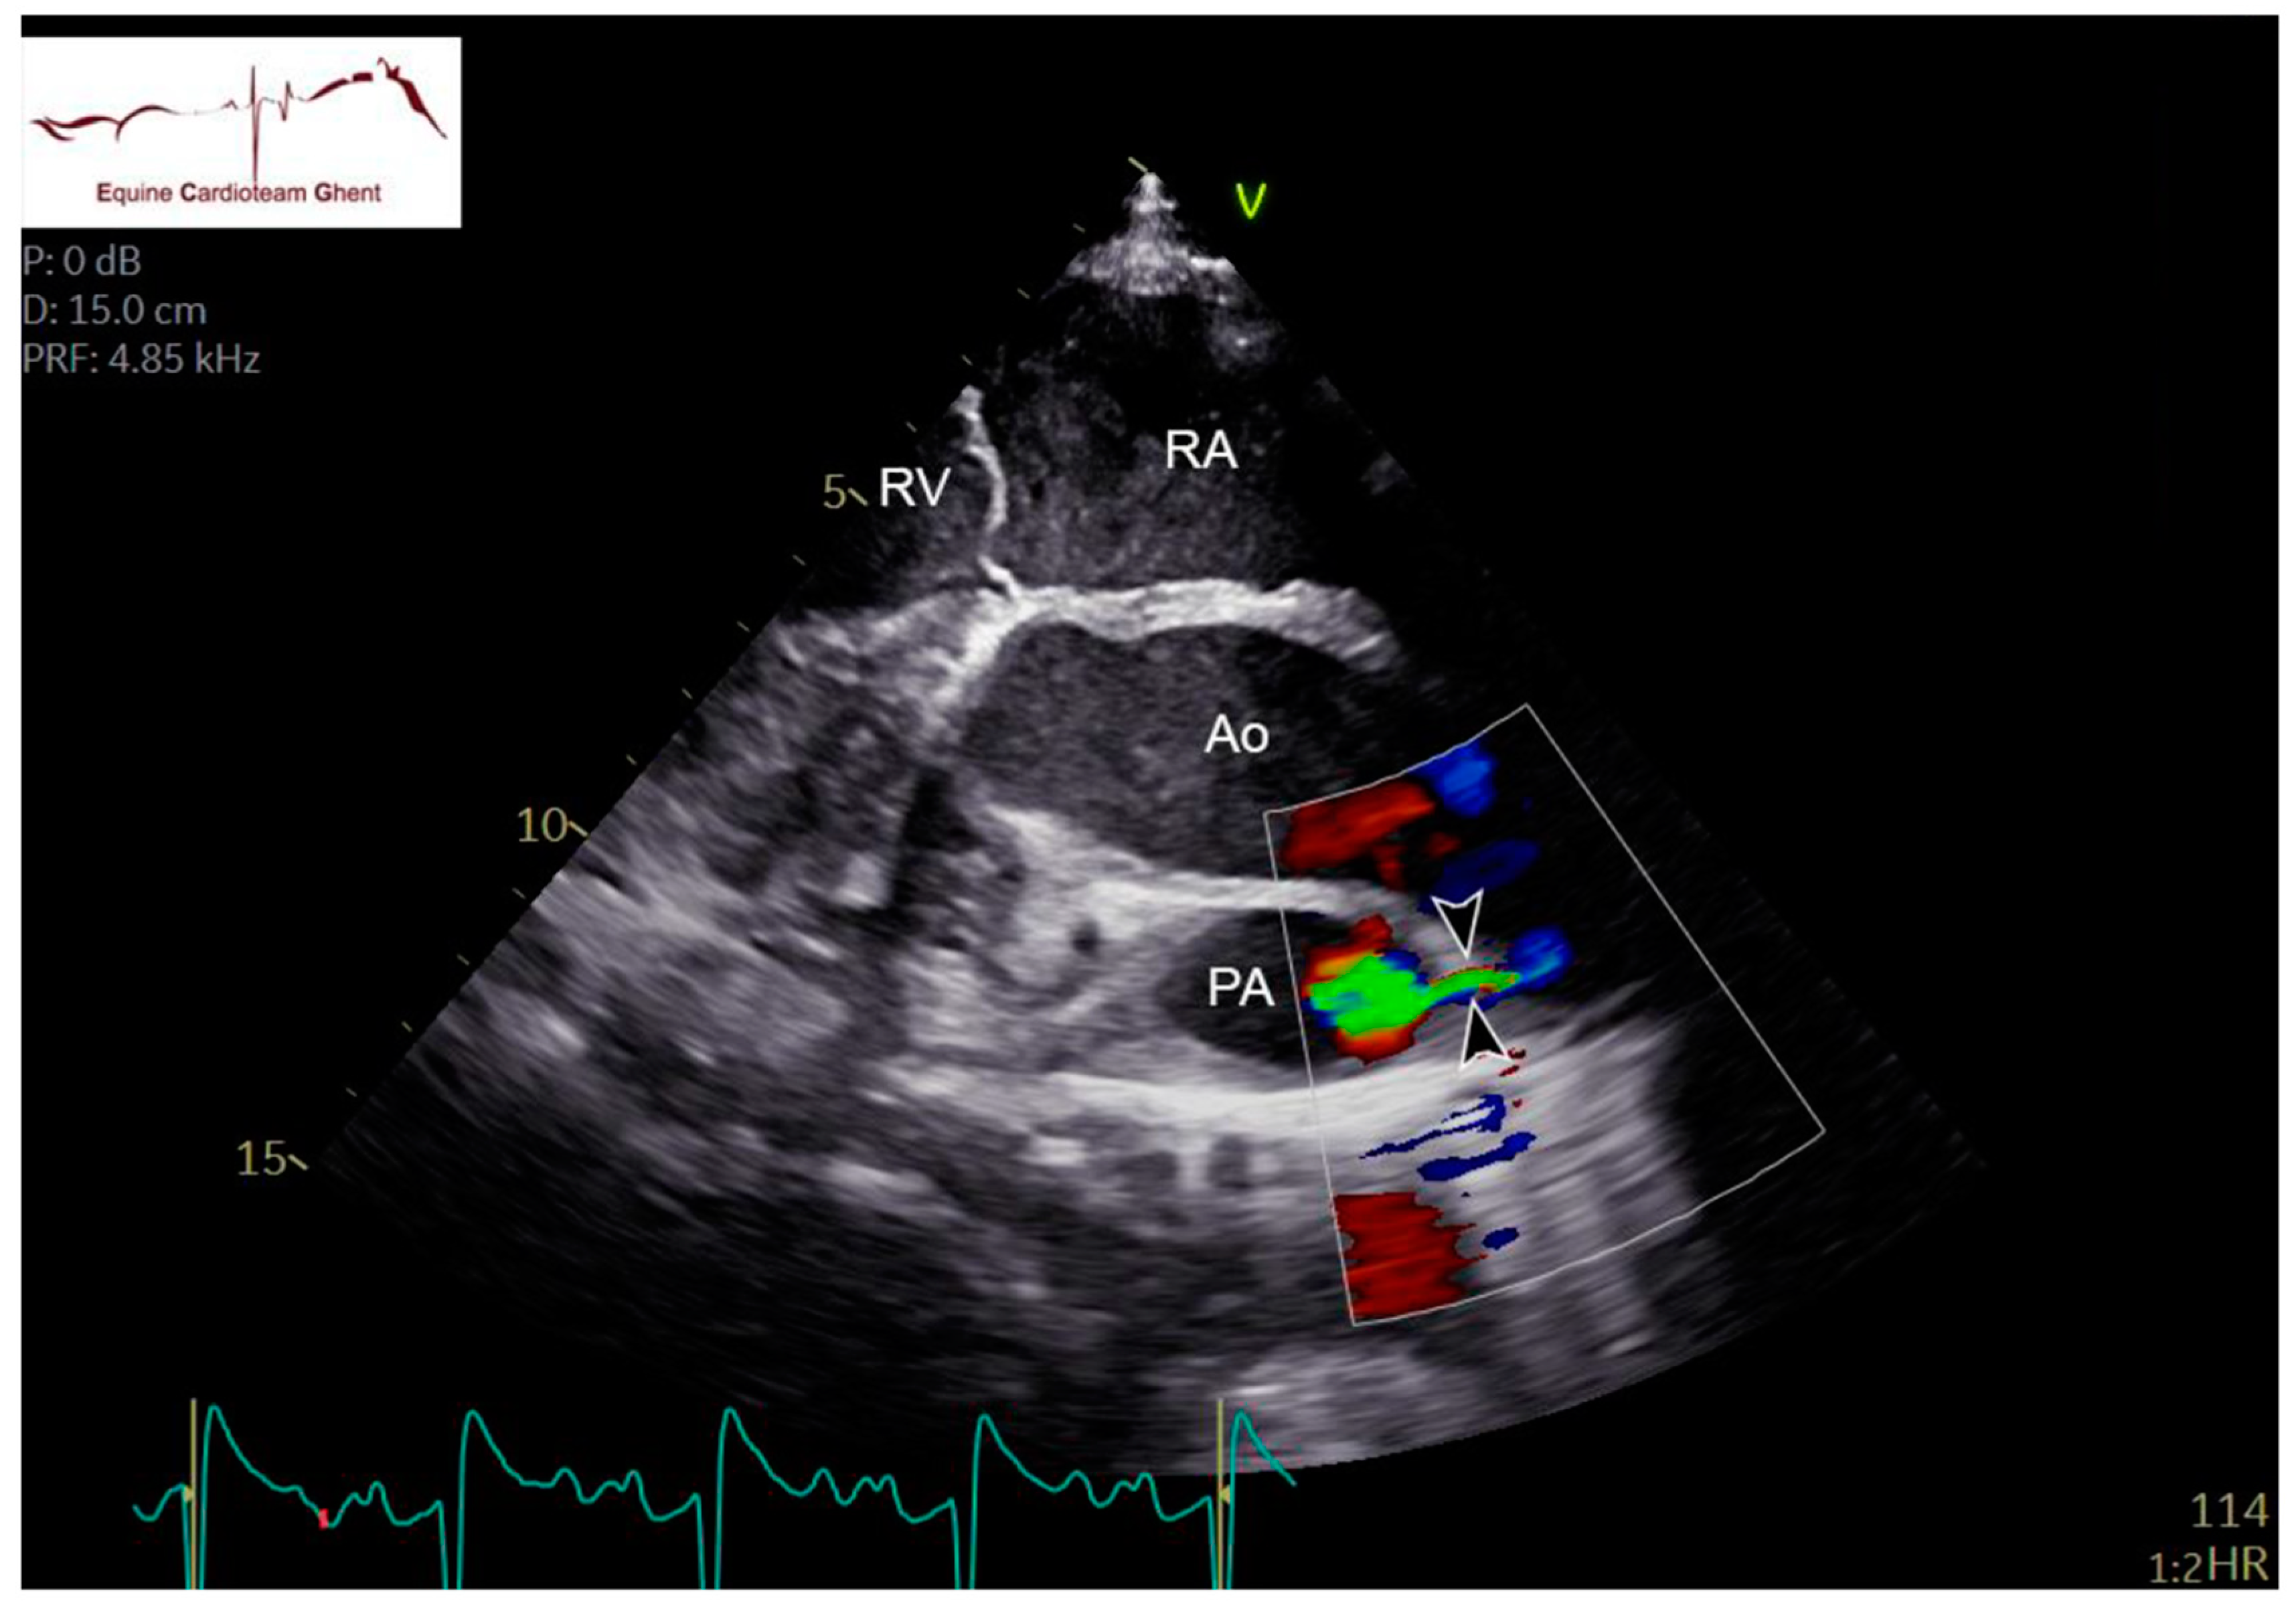

2.2. Echocardiography and Flow Doppler Examination

4. Discussion